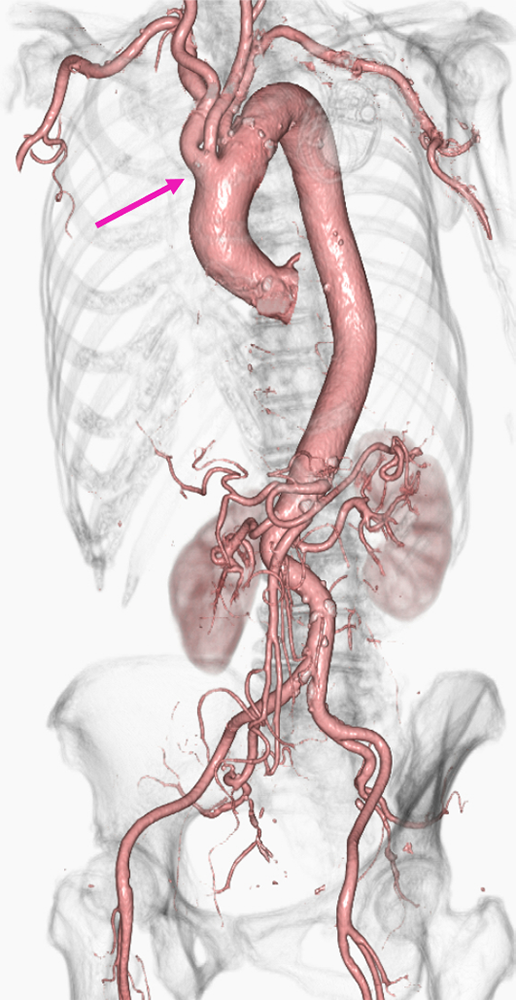

脳Perfusion+アクセスルートを造影剤1筒(100ml)で撮影した症例。最初に脳Perfusionを撮影後、Washoutを考慮して5分程度待ち、アクセスルートを撮影した。なお、アクセスルート撮影時の注入条件は、造影剤残量を加味しクロス注入法を用いている。脳Perfusion解析にはVitrea、脳血管および大血管3D作成にはザイオステーションを用いた。アクセスルートは頸部~脳血管+大血管を1回の息止めで完了できるようスキャン時間を短く設定してある。

急性期脳梗塞の診断はMRIが一般的だが、MRI非対応埋め込み型心臓電気デバイス (CIED) 留置中の患者へのMRI撮影は禁忌である。その場合、急性期梗塞の診断にはPerfusion CTが有用である。また、MRIと異なり、Perfusion CTでは同一セッションで血管内治療用の全身のアクセスルートの評価が可能である。

脳Perfusion+アクセスルートを造影剤1筒(100ml)で撮影した症例。最初に脳Perfusionを撮影後、washoutを考慮して5分程度待ち、アクセスルートを撮影した。なお、アクセスルート撮影時の注入条件は、造影剤残量を加味し、クロス注入法を用いている。脳Perfusion解析にはVitrea、脳血管および大血管3D作成にはザイオステーションを用いた。アクセスルートは頸部~脳血管+大血管を1回の息止めで完了できるようスキャン時間を短く設定した。